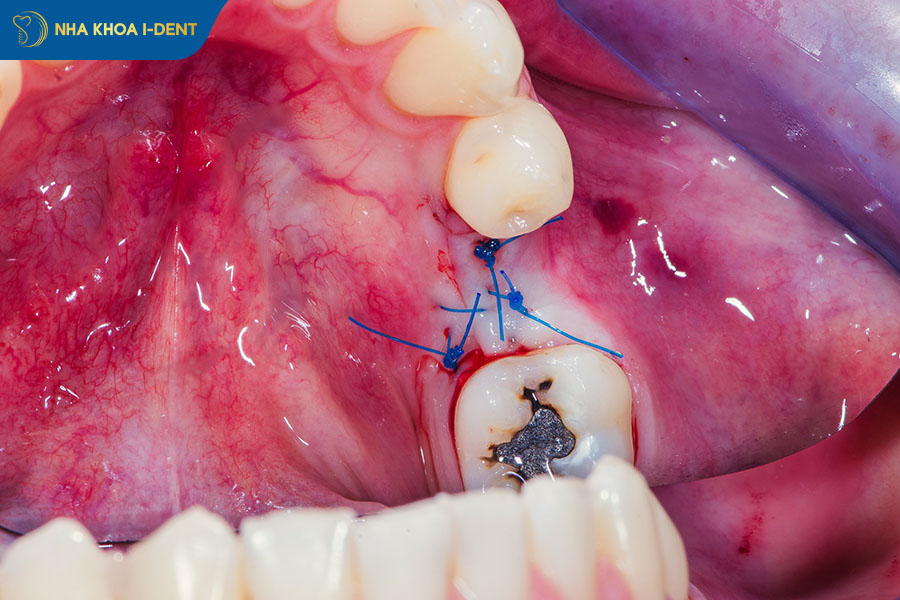

Công nghệ nhổ răng sóng siêu âm Piezotome là phương pháp nhổ răng khôn hiện đại bậc nhất hiện nay, sử dụng sóng siêu âm với tần số 28–36 KHz kết hợp mũi khoan siêu mỏng chỉ 0,2–0,5mm để bóc tách nhẹ nhàng phần nướu và dây chằng chân răng, giúp lấy răng khôn hàm trên ra ngoài mà không gây tổn thương đến mô mềm và xương xung quanh. Nhược điểm duy nhất của nhổ răng bằng công nghệ Piezotome là chi phí cao hơn so với phương pháp truyền thống.

Phương pháp nhổ răng khôn hàm trên bằng công nghệ sóng siêu âm Piezotome.